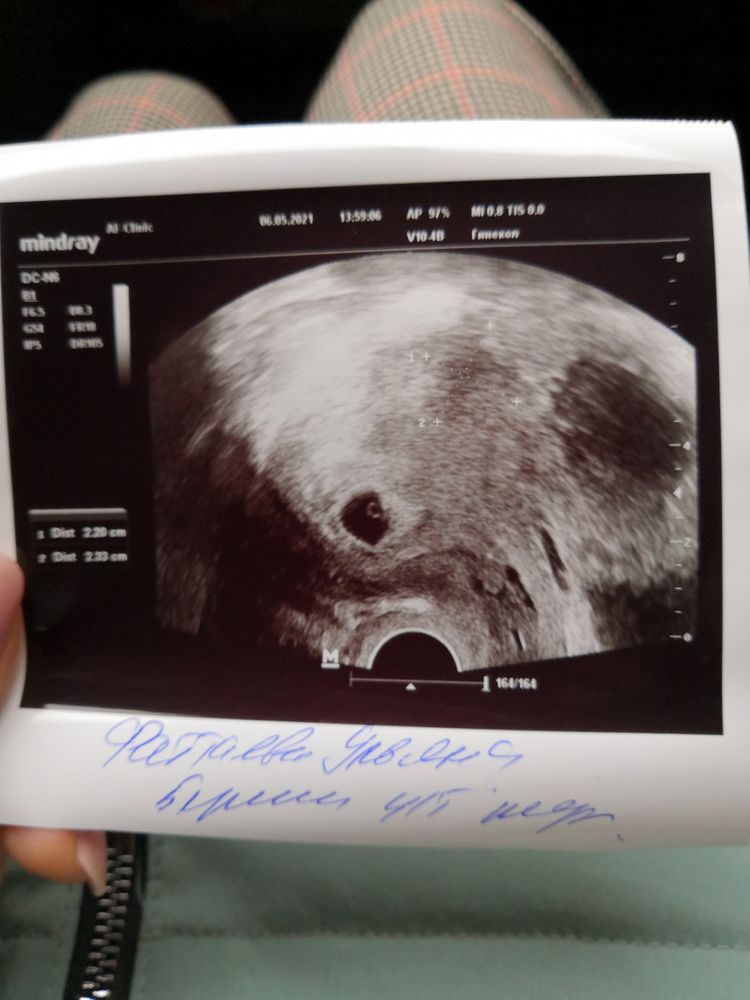

21дпп и первое УЗИ

Я БЕРЕМЕННА !Ну что,сходила на 1ое УЗИ,плодное яйцо в матке,про размеры и жм ничего не сказала,моя разговорчивая ре😅Повторное УЗИ 13го,слушать СБ🙈🙈🙈

Но самое фиговое,что на фоне Б выросла миома,2 см👿👿👿Вроде Б она никак не помешает,но обидно,только в 19ом году удалили🤦